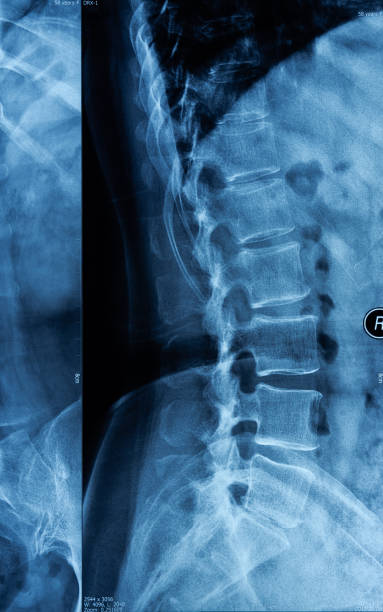

골반 통증 원인 두 번째는 천장관절증후군입니다. 천장관절 증후군 역시 허리디스크와 비슷한 통증으로 오인을 받을 수 있는데 천장관절 주변에 위치한 인대 손상, 관절의 불균형과 불안정성 대문에 허리와 엉덩이 주변으로 각종 통증이 생기는 질환을 의미합니다.

처장관절은 천골(엉치뼈), 장골(엉덩이뼈)가 만나는 부위로 외부 충격 혹은 골반이 힘을 주며 불편한 자세로 일어나거나 한쪽으로 체중이 쏠리는 잘못된 자세로 인하여 천장관절 주변으로 조직이나 인대 등에서 통증을 유발하는데 심할 경우 계단 오르내리는 것 자체도 어려워 질 수 있습니다.

허리디스크와의 구별은 허리디스크 환자는 아침에 일어날 때는 별다른 통증은 없으나 움직이면 통증이 심해지지만 천장관절증후군은 오히려 아침에 일어날 때 극심한 통증과 함게 기상하며 일상생활을 보내면서 증상이 완화되는 느낌이 난다는 것이 특징입니다.